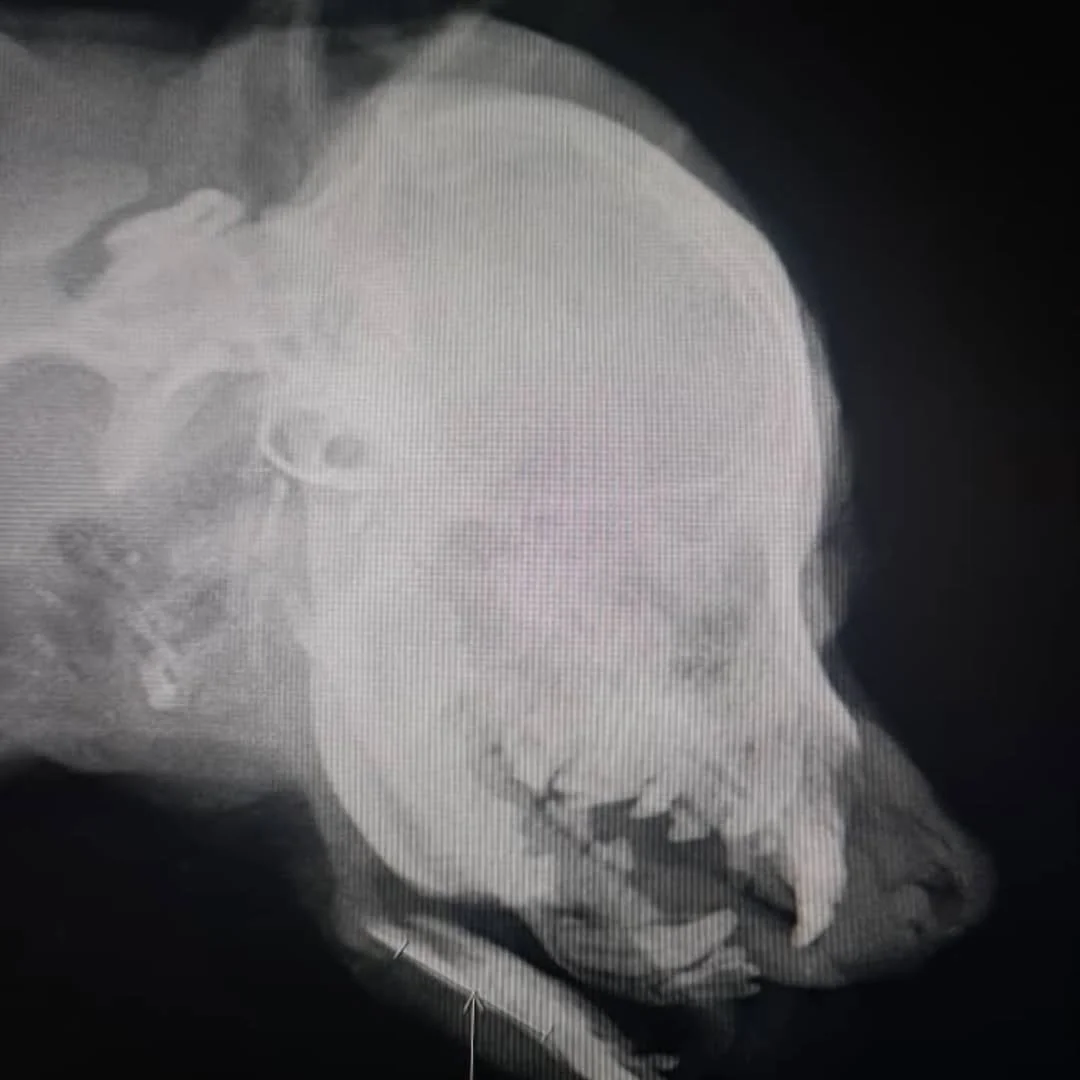

He was found in one of the worst conditions imaginable. Someone had struck him with a shovel, shattering his lower jaw until it hung loose, attached only by torn muscle. Rescuers feared the worst — that his jaw would need to be amputated, or that euthanasia might be the only option to end his suffering.

But compassion refused to give up. A skilled veterinarian spent over three hours in surgery, carefully piecing the shattered jaw back together. A week later, a second surgery was performed to stabilize the repair. What seemed impossible slowly became possible.

His case became more than a single rescue. The three-hour surgery taught the veterinary team a new method to repair severe jaw injuries before they progress to necrosis, amputation, or euthanasia. What was once thought impossible can now guide future treatments — giving other dogs with similar injuries a chance at survival.

Even when necrosis has already set in, as in this video and the following images, the approach can still allow part of the jaw to be removed minimally while saving as much as possible— preventing full amputation and giving the dog a chance to live.